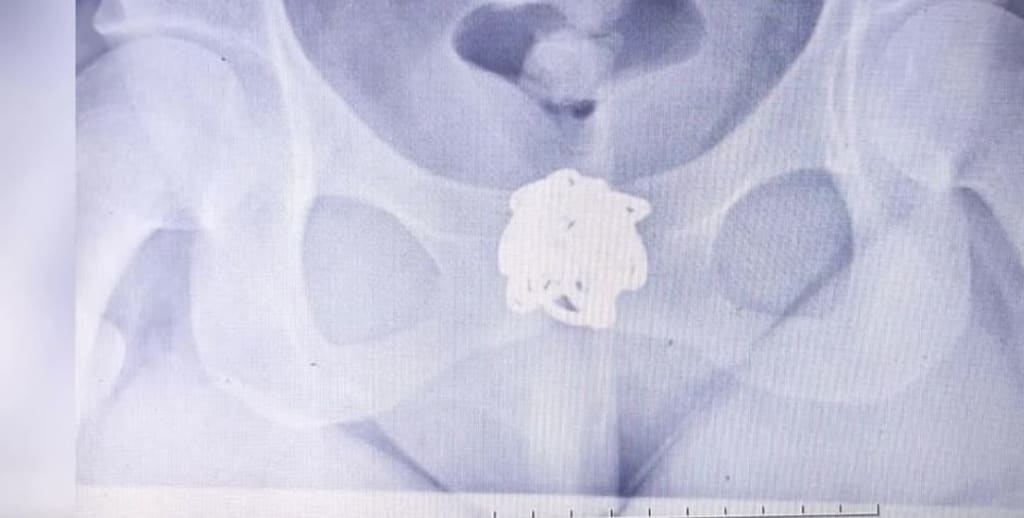

During this period, the patient began complaining of severe abdominal pain. She claimed the pain was unbearable and that she could no longer tolerate it. The emergency physician, taking her complaint seriously, ordered an urgent abdominal X-ray (KUB X-ray) to rule out any serious internal issues.

Under pressure and concern for the patient’s health, the X-ray was performed promptly. However, what the imaging revealed was shocking: the patient’s missing bracelet was clearly visible in her lower abdomen, specifically in the rectal area.

It became evident that the patient had intentionally hidden the bracelet inside her own body, presumably in an attempt to falsely accuse the hospital staff of theft and to claim financial compensation. This shocking discovery not only cleared the hospital staff of any wrongdoing but also revealed the patient’s deliberate attempt at fraud.